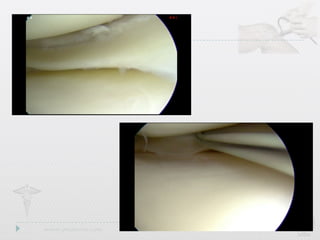

Radial Tears

• Also involvefree edge,but path is perpendicular to long axis • Drastically affect ability to resist hoop stresses • Deeper the tear,the more drastic the biomechanical consequences Radial Tears